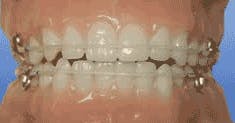

As a practicing general dentist, I see many adults whose chief complaint is crowding of the lower teeth — sometimes upper as well. Many received orthodontic care when they were younger and have not worn their retainers since then. Others never had any orthodontic treatment, yet complain that their lower teeth are suddenly becoming crowded.